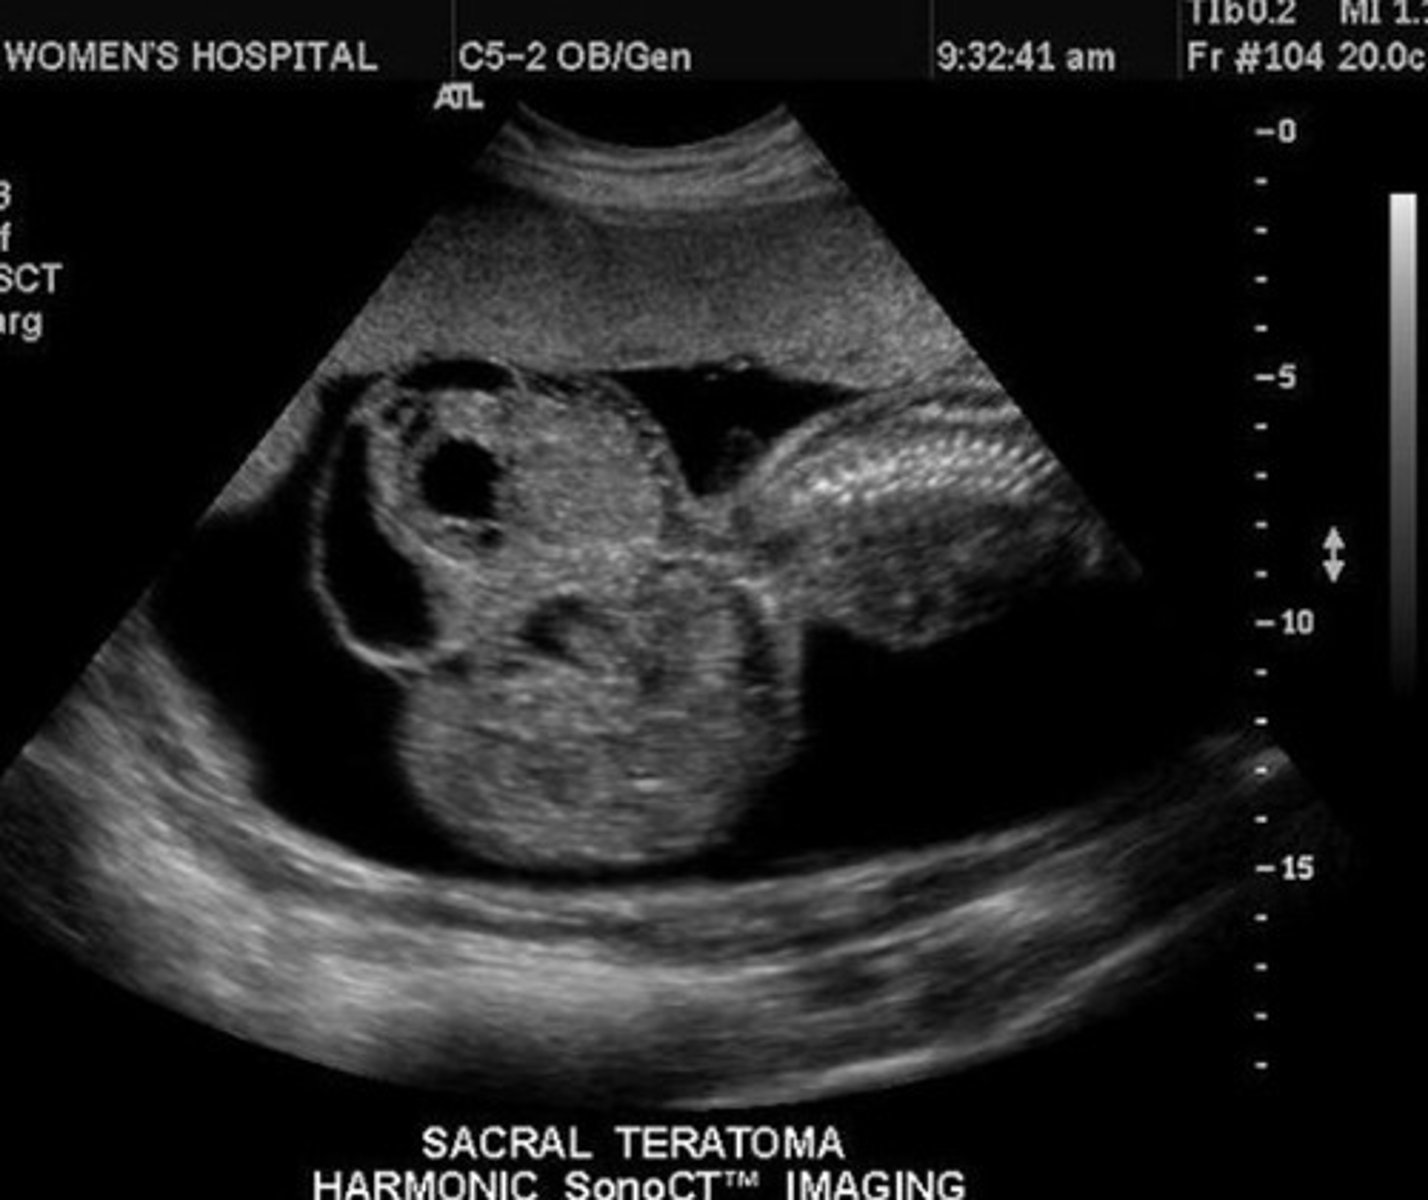

Sacrococcygeal Teratoma

Large complex mass

Arises from sacral spine